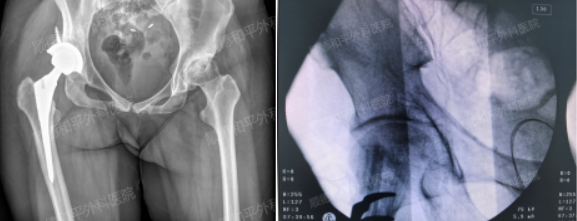

髋置换&保髋治疗

切取的左侧腓骨

全面且详细的检查结果,完整的说明了患者尚在股骨头坏死早期,手二区何明飞主任团队决定为其实施“保髋”治疗,通过清除坏死骨质、植入自体髂骨联合PRP(富血小板血浆)及带血管蒂的腓骨瓣移植,重建股骨头血运,最大程度保留髋关节功能。

术后,患者恢复顺利,术后1周卧床休养,10天后可逐步扶拐下地活动,2周拆线后即可出院。未来通过定期复查(6周、3个月、6个月等),预计6-9个月后可逐渐脱拐行走,实现功能康复。

这一术式不仅能修复受损骨结构,更通过显微外科血管吻合技术重建股骨头血运,有效避免病情恶化,帮助患者保留自身髋关节功能,减少长期卧床与关节置换的风险。